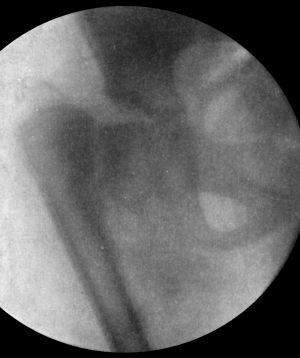

148 76.Radiogram of Steinmann's Apparatus applied for Direct Extension to the Femur

150 77.Hodgen's Splint